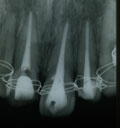

4.11年後

中央二本の根の部分の、所々に小さな虫食い状が見られます.

虫歯でなく、吸収といいます。 |